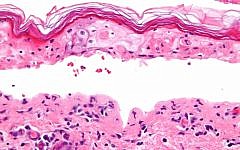

אילו תרופות אנטי אפילפטיות גורמות להפרעות עוריות חמורות?

החוקרים ביצעו ניתוח רטרוספקטיבי של מאגר יפני המתעד תופעות לוואי במטרה לבדוק אילו תרופות אנטי אפילפטיות קשורות באופן חזק להופעה של תסמונת סטיבן-ג'ונסון ולנמק עורי רעיל בילדים